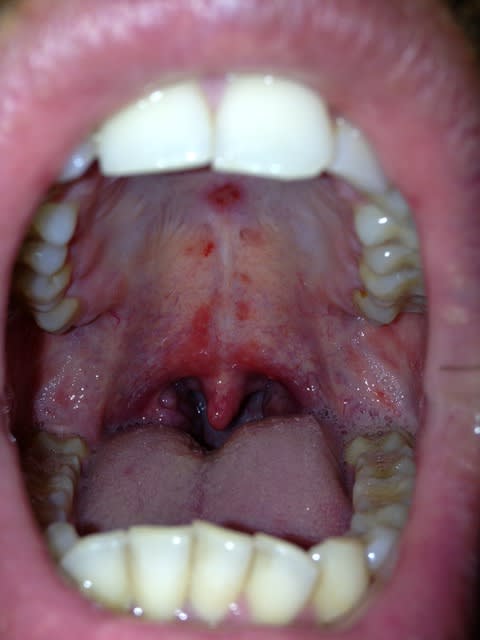

un ami présenté les lésion suivante au palais.

lésion légèrement sensible , avec petit démangeaison

et léger mauvais gout.

il prend actuellement un anti inflammatoire : tilcotil

désolé pour la qualité de photos ca a été fait a la va vite a l'iphone